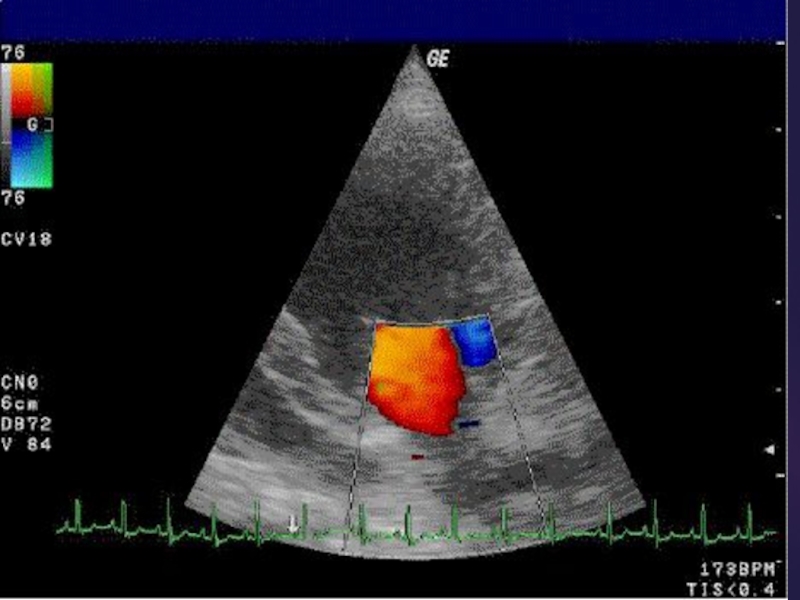

Слайд 14УЗИ сосудов

исследуются магистральные и внутриорганные сосуды: их размеры, расположение, состояние

просвета.

УЗИ сосудов исследуются магистральные и внутриорганные сосуды: их размеры, расположение, состояние просвета.